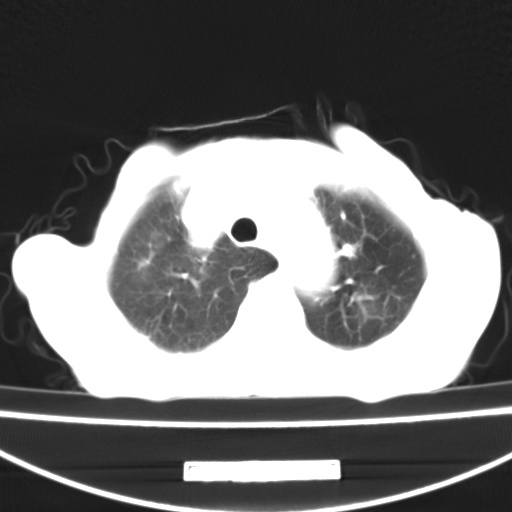

患者 女 67岁,反复咳嗽咳痰2年,加重伴喘及双下肢浮肿1月

诸大血管及f肺门血管增粗迂曲.左下肺多发薄壁空腔影.部分非也透亮度增高.薄曾扫描可区分肺气肿类型.考虑1.慢性支气管炎 2.左下肺支气管扩张 3.肺气肿 4 肺动脉高压5.是否有先心病病史

考虑1.慢性支气管炎 2.左下肺支气管扩张 3.肺气肿 4 肺动脉高压

慢支炎、肺气肿、双肺感染、左下囊状支扩。

慢支、肺气肿、肺动脉高压;左下肺囊状支扩并粘液栓形成。